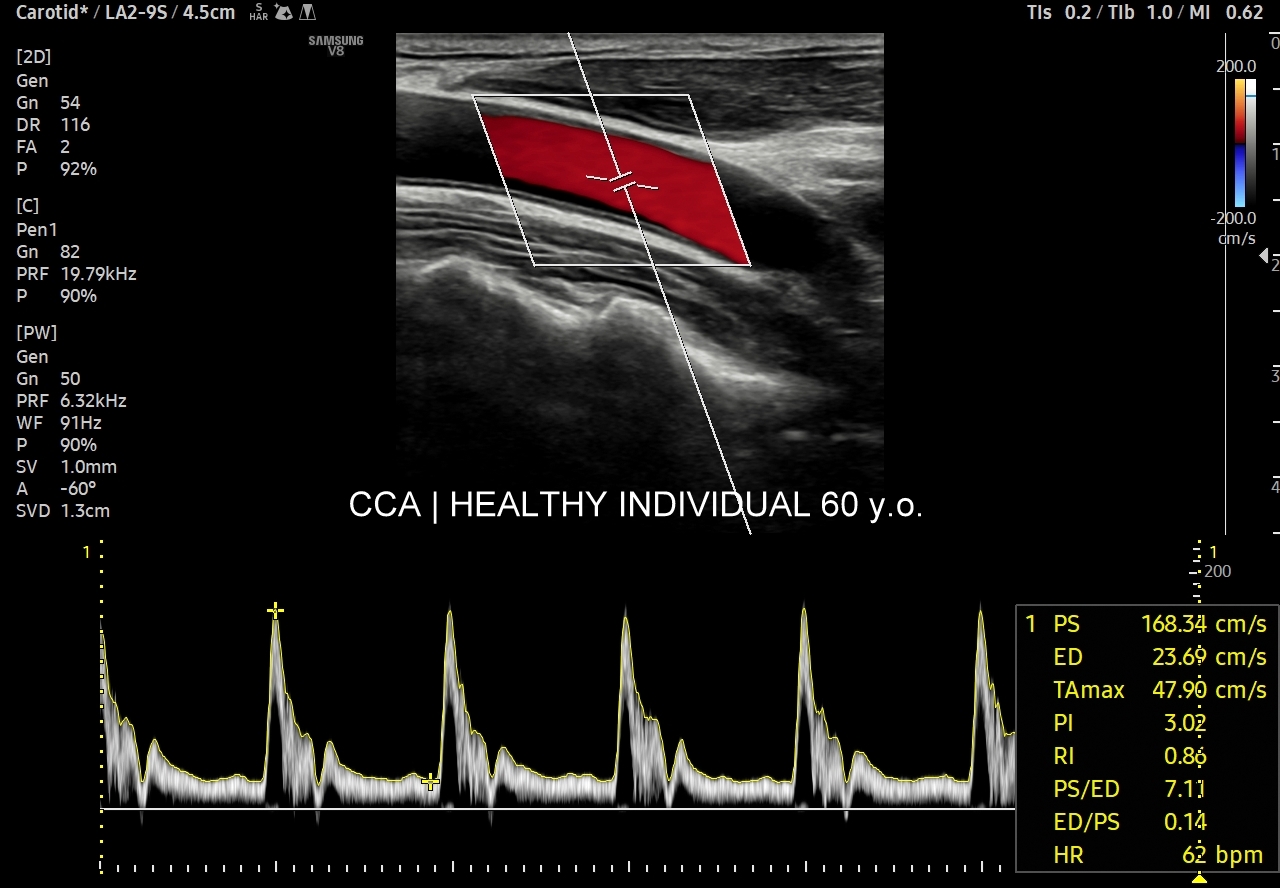

Oprócz przepływów typowo niskooporowych oraz typowo wysokooporowych istnieją profile przepływów o pośredniej charakterystyce, np. w tętnicy szyjnej wspólnej. Z kolei w przypadku tętnic kręgowych w zależności od ich szerokości fizjologicznym jest obserwowanie zarówno profilu niskooporowego w przypadku dużej średnicy, jak i wysokooporowego w przypadku małej średnicy.

Profil przepływu tętniczego cechuje się pulsacyjnością. W składu pulsu wchodzi składowa skurczowa i rozkurczowa. Składowa skurczowa rejestrowana jest we wszystkich drożnych tętnicach i jest zależna głównie od prawidłowo funkcjonującego serca. Składowe rozkurczowe, a konkretnie kształty spektrum prędkości przepływu krwi w naczyniach w trakcie rozkurczu komór serca, różnią się w zależności od łożyska naczyniowego. Otóż składowa rozkurczowa zależy przede wszystkim od unaczynionej przez tętnicę tkanki bądź narządu, a także od kurczących się elastycznych tętnic. Pomiędzy składową skurczową a rozkurczową często obserwuje się złamki odpowiadające chwilowemu wstecznemu przepływowi krwi związanemu z zamykaniem się zastawek aortalnej bądź płucnej, jak i odbiciem się fali tętniczej od naczyń na poziomie mikrokrążenia (ang. water-hammer effect). Biorąc pod uwagę kształt fali spektrum przepływu możemy je podzielić na te o 1/ niskiej pulsacyjności, 2/ umiarkowanej pulsacyjności, 3/ wysokiej pulsacyjności.

Pulsacyjność przepływu można oceniać ilościowo używając wskaźnika pulsacyjności Goslinga PI (ang. pulsatililty index) lub jednostki pochodnej w postaci wskaźnika oporu Pourcelota RI (ang. resistance index). Synonimem profili o niskiej pulsacyjności są profile niskooporowe. O profilach z umiarkowaną i wysoką pulsacyjnością można mówić, iż są wysokooporowymi.

Kolejnym i bardzo ważnym wskaźnikiem określającym przepływ w naczyniu tętniczym jest wspomniany już opór przepływu. Jego kwantyfikacja w postaci określenia wskaźnika oporu RI wykorzystywana jest praktycznie przy badaniu funkcji miąższowych narządów wewnętrznych w organizmie (np. nerki, wątroby, mózgu), a także w ramach oceny biologii tkanek nowotworowych, czy zapalnych w celu przeprowadzenia tzw. oceny multiparametrycznej MPUS. Otóż w przypadku narządów, głównie miąższowych, o stałym lub/i wysokim metabolizmie przepływ tętniczy poza szczytem skurczowym utrzymuje się stale w okienku rozkurczowym. Im mniejsza różnica pomiędzy szczytową prędkością skurczową (PSV, peak systolic velocity) a prędkością końcowo-rozkurczową (EDV, end diastolic velocity) tym niższy jest opór i wskaźnik oporu, który to wylicza się z następującego wzoru: RI = (PSV-EDV) / PSV.